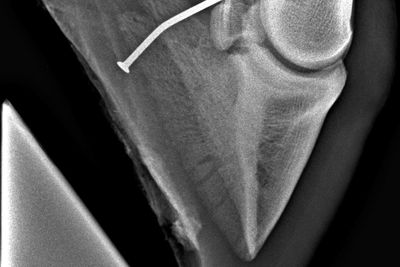

Die Strahlbeinfraktur

Ein Bruch des Strahlbeins oder sogenannten Hufrollenknochens am Hinterbein ist grundsätzlich sehr selten. In diesem Fall lag seit längerem eine deutliche Lahmheit am Hinterbein vor.